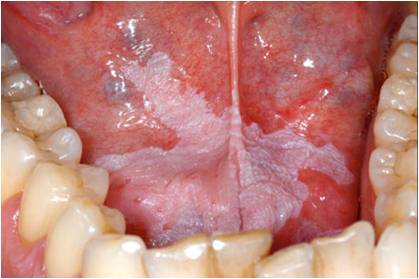

口腔白斑病

口腔白斑

口腔白斑病一侧口腔黏膜网状白斑图.jpg

口腔毛状白斑

口腔毛状黏膜白斑口腔毛状粘膜白斑2022已更新今日图集